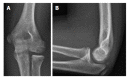

Osteochondritis dissecans (OCD) is a disorder of articular cartilage and subchondral bone. In the elbow, an OCD is localized most commonly at the humeral capitellum. Teenagers engaged in sports that involve repetitive stress on the elbow are at risk. A high index of suspicion is warranted to prevent delay in the diagnosis. Plain radiographs may disclose the lesion but computed tomography and magnetic resonance imaging are more accurate in the detection of OCD. To determine the best treatment option it is important to differentiate between stable and unstable OCD lesions. Stable lesions can be initially treated nonoperatively with elbow rest or activity modification and physical therapy. Unstable lesions and stable lesions not responding to conservative therapy require a surgical approach. Arthroscopic debridement and microfracturing has become the standard initial procedure for treatment of capitellar OCD. Numerous other surgical options have been reported, including internal fixation of large fragments and osteochondral autograft transfer. The aim of this article is to provide a current concepts review of the etiology, clinical presentation, diagnosis, treatment, and outcomes of elbow OCD.